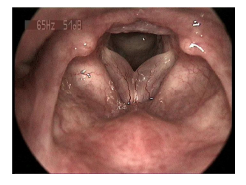

Paciente do sexo feminino, 48 anos, tabagista, apresenta rouquidão importante há alguns meses. Diante desta videolaringoscopia, qual o diagnóstico?